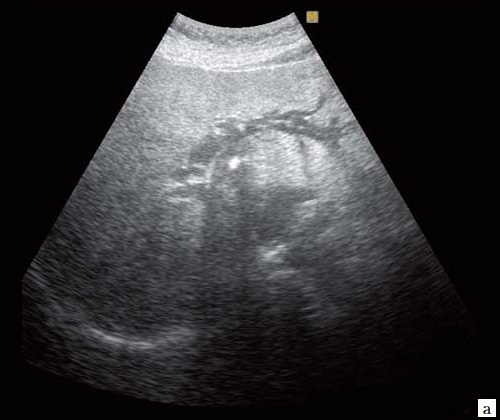

- Ультразвуковое исследование (УЗИ). Основным признаком МЖ при УЗИ является расширение внутрипеченочных желчных протоков (рис. 1). УЗИ позволяет не только выявить билиарную гипертензию, но и установить уровень блока. При высоком билиарном блоке (обтурация на уровне ворот печени) при УЗИ визуализируются расширенные внутрипеченочные протоки при нормальном диаметре ОЖП (до 6 мм), желчный пузырь чаще нормальных размеров или уменьшен, возможно выявление в воротах печени объемного образования.При низком билиарном блоке (обтурация на уровне холедоха, головки ПЖ, БДС) кроме расширенных внутрипеченочных протоков визуализируются расширенные внепеченочные протоки, желчный пузырь увеличен (рис. 2). Если низкий блок обусловлен индуративным панкреатитом, при УЗИ имеет место увеличение органа в размере, могут выявляться кальцинаты в ПЖ (рис. 3). При опухоли головки ПЖ на фоне билиарной гипертензии визуализируется объемное образование в ПЖ (рис. 4). Критериями гипертензии главного панкреатического протока служит его расширение более 2 мм в теле и более 3 мм в головке ПЖ.При ЖКБ, осложненной холедохолитиазом, выявляется увеличенный желчный пузырь с конкрементами, а также конкременты в холедохе (рис. 5).Диагностируют очаговые поражения печени: эхинококковые и альвеококковые кисты; увеличенные лимфоузлы; местатазы.

Рис. 1. Ультразвуковая картина билиарной гипертензии при механической желтухе.